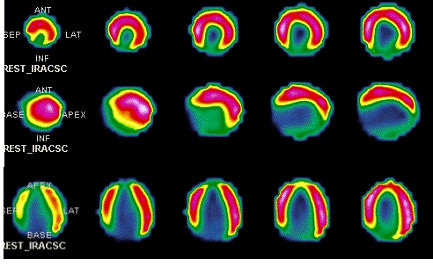

Радионуклидная диагностика

Радионуклидная диагностика (РНД) - группа

методов, основанная на регистрации изображений от объектов, излучающих

гамма-лучи (хорошо проникающих через ткани). Для того, чтобы человеческий

организм стал источником излучения, в него вводятся радиофармацевтические

препараты (РФП), содержащие в своем составе радионуклиды. Идеальный РФП

распространяется только в пределах органов и структур, предназначенных для

визуализации (органотропные препараты). В онкологической практике особое место

занимают канцеротропные препараты, дающие накопление в злокачественных

новообразованиях. Многие из этих методов отличаются высокой чувствительностью

при низкой специфичности и при низком пространственном разрешении. Основное

предназначение РНД - оценка функционального компонента патологических

изменений.

Эмиссионные компьютерные томографы оснащены

системой вращения встроенной в них гамма-камеры и позволяют реконструировать

секционное изображение. Помимо функциональных исследований различных органов

(щитовидная железа, гепатобилиарная система, молочная железа, легкие, система

кровообращения и др.) может быть получена ценная информация о структурных нарушениях.

Позитронные эмиссионные томографы основаны на

использовании испускаемых радионуклидами позитронов (испускаемый протон сразу

же реагирует с ближайшим электроном в реакции аннигиляции; излучаемые при этом

два гамма-фотона регистрируются двумя детекторами). Для производства

радионуклидов на ПЭТ используются циклотроны. Данный вид томографии позволяет

подробно изучать скрытые метаболические процессы.

Радионуклеидная диагностика